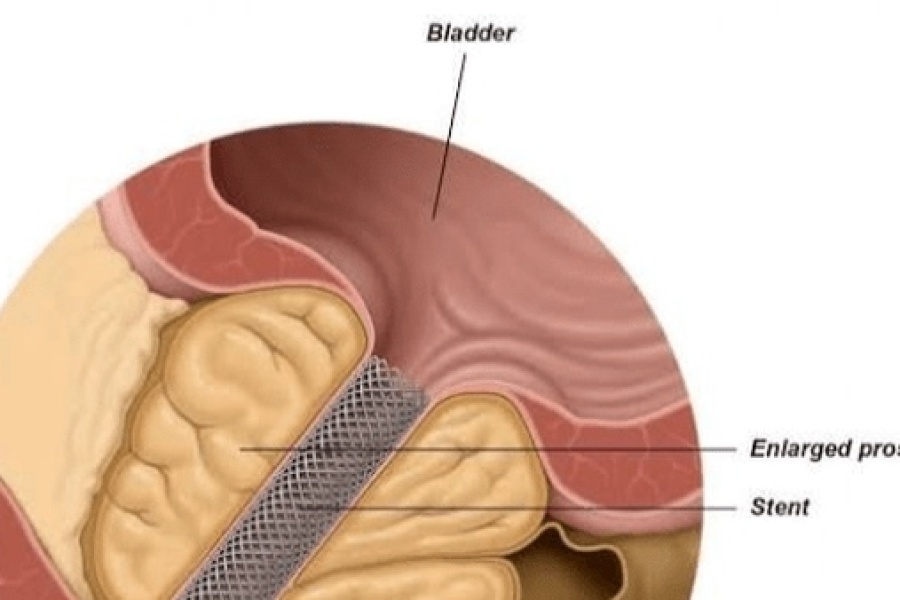

سلامت گیل/ به نقل از فارس؛ فارس،اکبر نورعلی زاده فلوشیب اندویورولوژی و رییس شانزدهمین کنگره اندویورولوژی در نشست خبری بیان کرد: سرطانهای دستگاه ادراری و بزرگی پروستات در مردان و شایعترین سرطان دستگاه ادراری پروستات ایت و کشندهترین سرطان سرطان نیز در دستگاه ادراری در مردان مثانه و کلیه است.

حمید پاک منش دبیر کنگره در سه روز برگزار میشود.مشکل کنونی کمبود تکنولوژی است اما تعداد اندریولوژیست در کشور مطلوب است اما امکاناتی برای جراحیهای پیشرفته مانند جراحی رباتیک و در برخی استانها لیزر وجود ندارد.در کشوری زندگی میکنیم که یا توجه به آب و هوا و ژنتیک سنگ کلیه شایع است و اگر کوچکترین علایمی از درد پهلو و خون در ادرار حتما به پزشک مراجعه کنید.در بسیاری موارد میتوان دارو تجویز کرد اما فردی که یکبار سنگ کلیه ساخته احتمال مجدد وجود دارد و توصیه میکنیم هر سه ماه سونوگرافی بدهد.